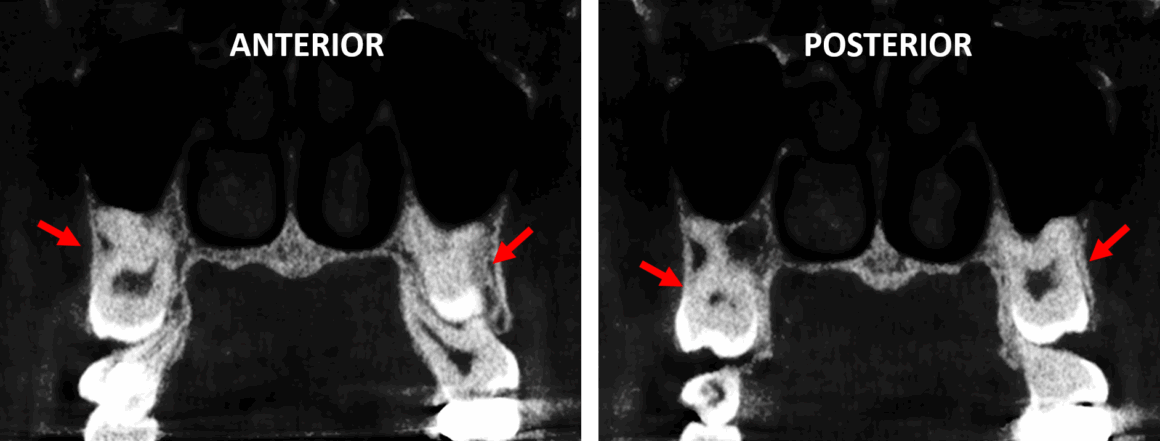

En la evaluación con tomografía del maxilar superior, se realizó la reconstrucción panorámica (Fig.1) donde se observan los órganos dentaros 18 y 28 (flechas rojas) retenidos en posición vertical impactados contra los órganos dentario 17 y 27. Nótese el tratamiento de conducto en el órgano dentario 17.